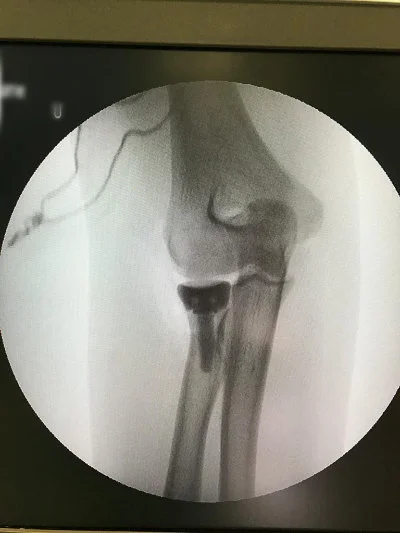

Görüntüleri büyütmek için resmin üstüne tıklayınız.